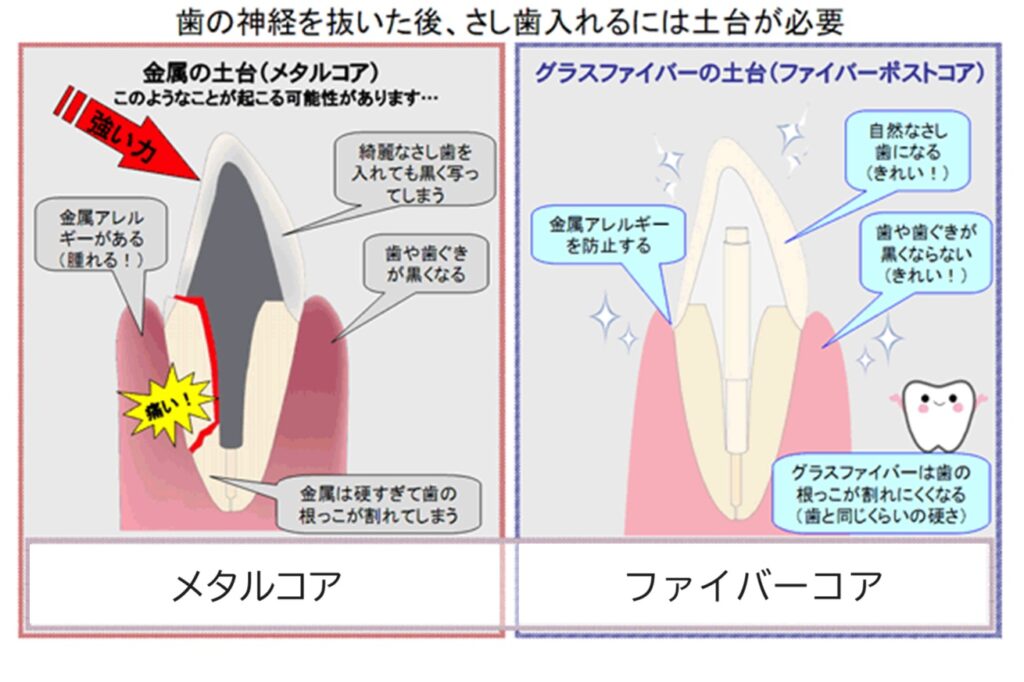

※メタルコアとは

神経を取った歯を、いわゆる差し歯にするために、歯の中に金属の柱を植え込む治療法です。

現在でも行われる治療方法で、昔は金属を用いることが多かったですが、

近年ではファイバーコアという、グラスファイバーの材料を使うことが多くなってきました。

当院ではメタルコアを外して、治療をやり直すことが多いです。

せっかく歯を綺麗にやり直す場合、

例えば、家をリフォームする場合、家の基礎をやり直した方が、将来的に長持ちする可能性があります。特に古く保険でされた治療は精度が悪い場合も多く、新しい材料でやり直した方が安心だったりします。

しかし、メタルコアを外すことはリスクも伴います。

外す際に歯に負担がかかると、歯が割れてしまう場合もあります。